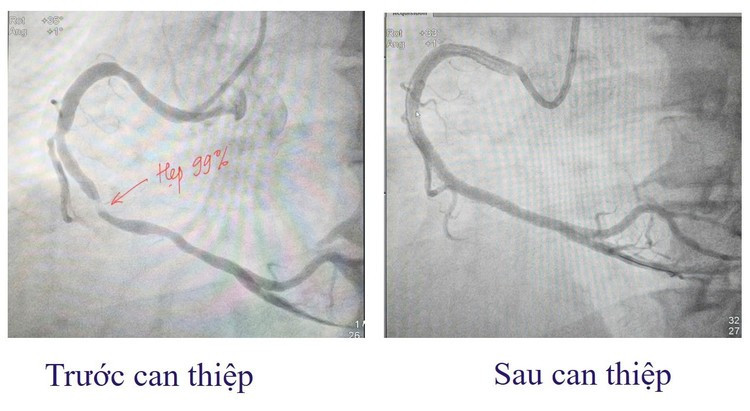

Ngay lập tức, anh được cấp cứu theo phác đồ hội chứng vành cấp và chỉ định chụp động mạch vành qua da cấp cứu. Kết quả, động mạch vành phải (RCA) đoạn 2-3 hẹp tới 99%, đoạn 1 hẹp 60%. Đây là tình trạng tắc hẹp mạch vành nguy kịch, có thể dẫn đến hoại tử cơ tim lan rộng, đe dọa tính mạng nếu không được can thiệp tái thông mạch máu kịp thời.

Hình ảnh mạch máu trước và sau can thiệp - Ảnh BVCC